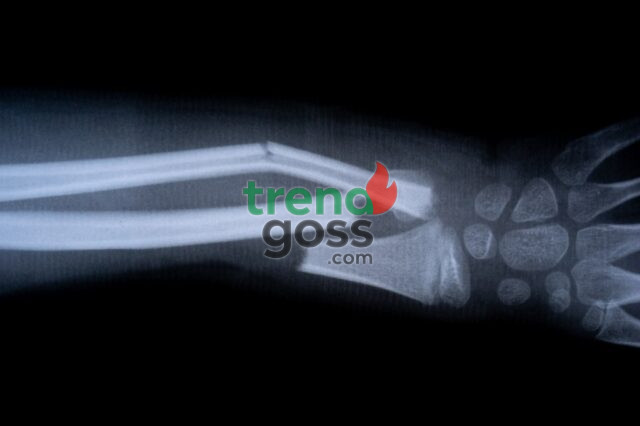

In one trial, a patient with a wrist fracture was treated through a small incision. Instead of metal plates and screws, Bone-02 was used, and the bone healed within minutes. Three months later, doctors confirmed the patient had fully recovered without any complications.